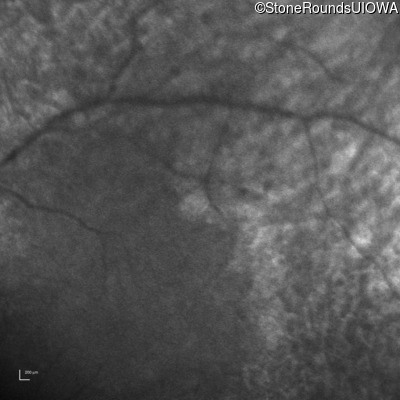

Infrared Fundus Photograph - Right -

No Light Perception

Exemplar

Infrared Fundus Photograph - Left -

Light Perception